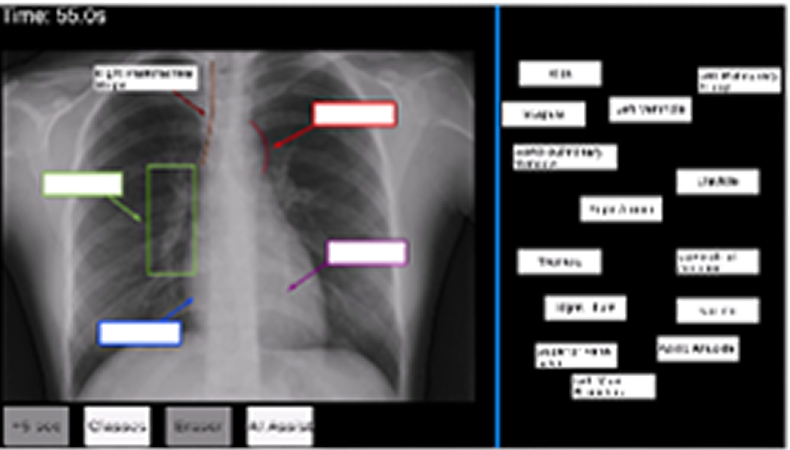

Labeling key anatomical landmarks for lines and tubes interpretation on chest X-rays

Recognizing normal/abnormal positioning of lines and tubes and their tips to teach accurate image interpretation